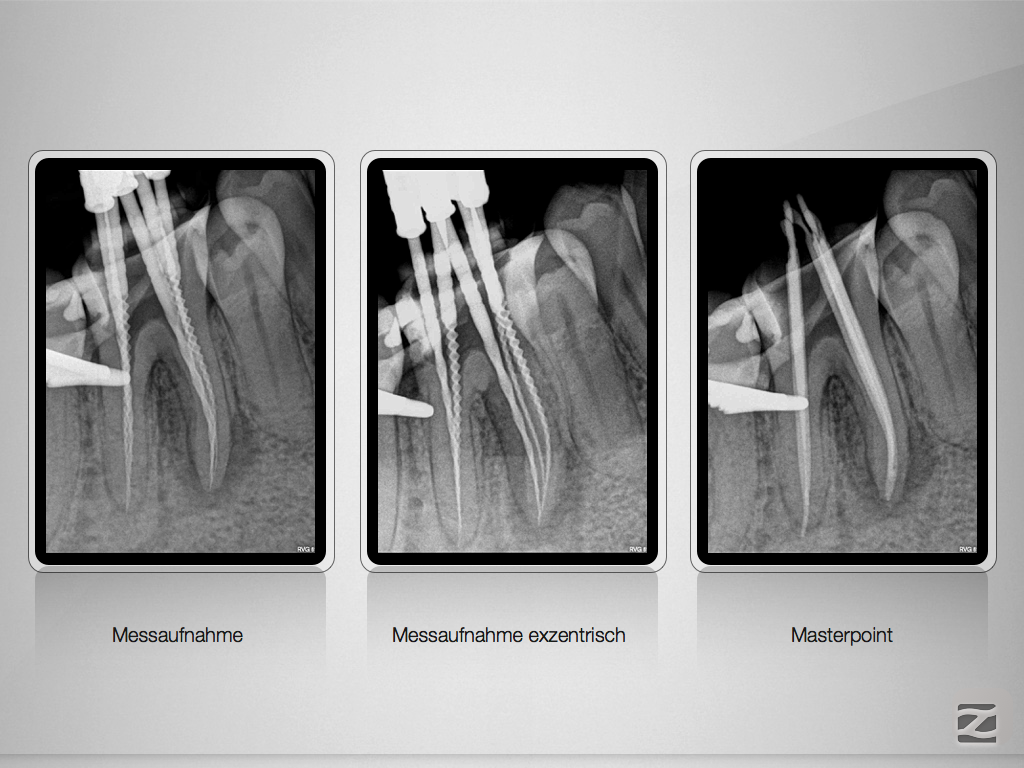

46D.005

Partielle Pulpanekrose